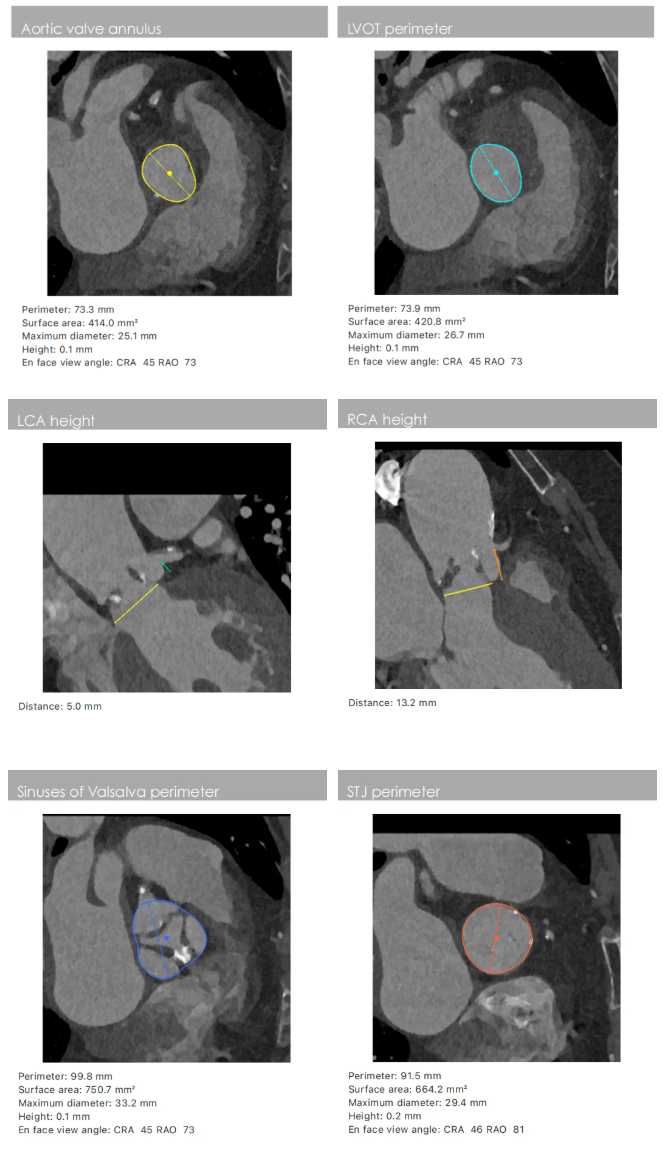

患者主动脉瓣重度狭窄并重度反流。CT显示三叶瓣,瓣叶增厚、中度钙化集中在瓣叶边缘与左无交界融合处,瓣环周长73.7 mm,均径23.4 mm,LVOT(左室流出道)周长73.9mm,STJ(窦管交界)周长91.5mm,升主动脉均径120.8 mm,瓣环角度可。左冠瓣叶长,LCA开口较低,有一定风险。